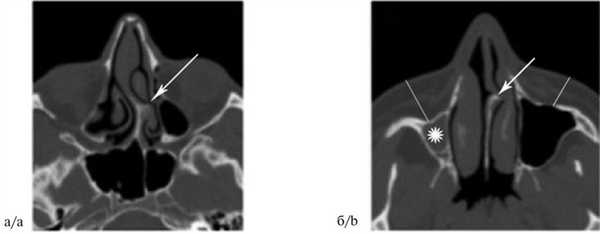

Больной К., 39 лет, 7 декабря 2015 г. поступил в БМУ «Курская областная клиническая больница» с жалобами на постепенно ухудшающееся дыхание через левую половину носа в течение последних 10 лет. При передней риноскопии определялась полная обструкция левого общего носового хода деформированной перегородкой носа. На К.Т. от 10 декабря 2015 г. была выявлена деформация перегородки носа с формированием шипа, который фенестрировал среднюю носовую раковину и деформировал ННР. Хрящевая пластинка точно повторяла кривизну костного шипа, была более утолщенной, чем в других отделах (рис. 2). Правая верхнечелюстная пазуха гипоплазирована, полностью заполнена патологическим содержимым. Верхнечелюстной костный комплекс выглядел асимметричным (слева более развит), при этом внешней асимметрии лица не наблюдалось из-за более развитых мягких тканей на правой стороне лицевой области, что хорошо видно на КТ (см. рис. 2, б).

Рис. 2. Больной К., 39 лет. Компьютерная томограмма околоносовых пазух, аксиальная проекция. Костный шип перегородки носа (указано стрелками) перекрывает общий носовой ход, при этом фенестрирует среднюю носовую раковину и деформирует ННР. Правая верхнечелюстная пазуха гипоплазирована (указано звездочкой), объем мягких тканей лицевой области асимметричен (указано линиями). Fig. 2. Patient K., aged 39 years. CT of the paranasal sinuses in the axial projection. The spur of the nasal septum (shown by arrows) obstructs the common nasal passage, causes the fenestration of the middle turbinated bone, and deformation of the inferior turbinated bone. Hypoplasia of the right maxillary sinus (denoted by the asterisk) and asymmetric volume of the soft tissues in the facial region (shown by lines).

На основании результатов обследования выставлен диагноз: искривление носовой перегородки, вторичная деформация левой ННР, гипоплазия правой верхнечелюстной пазухи. От дальнейшего обследования и лечения пациент отказался.